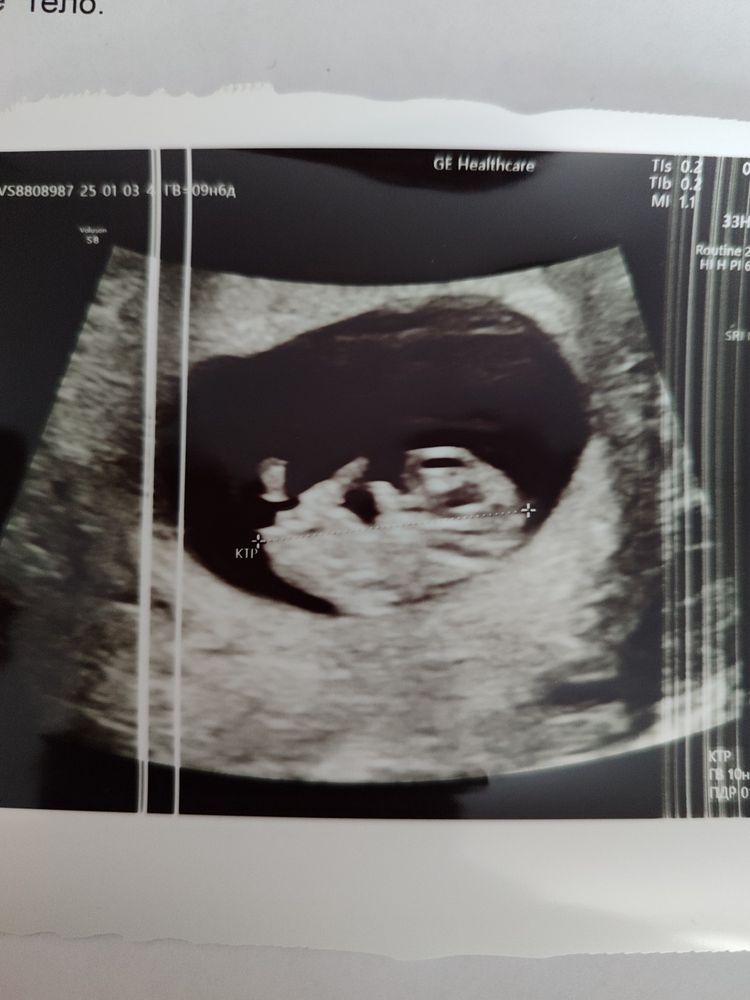

жду девочку, 13 неделя Уфа

Плодное яйцо

Конечно, выглядит абсолютно не тесно)) на таком сроке ПЯ уже не важно, уже КТР смотрят. Все хорошо у вас♥️ и чсс к скринингу вообще к 160 спуститься

Разница между КТР и ПЯ в 4 дня это ерунда полная, обычная погрешность в замерах. ЧСС - тоже в пределах нормы.

Аля, ну у меня даже с отставанием в 2 недели не замерла беременность, но были сильные отслойки и кровотечения, ни к чему хорошему это бы не привело, было принято решение вызывать роды по мед показаниям. Потому что на любом сроке мог или замереть или бы непонятно какой ребёнок родился бы. У вас на узи хорошее большое пя там и не пахнет отсутствием места. Как правило отставание пя - это генетическая ошибка и от вас уже ничего не зависит, поэтому нет смысла нервничать. Но еще раз повторяю - отставание 5 дней - это не отставание. Мне узист опытный говорил, что разница между ктр и пя до недели - это норма.